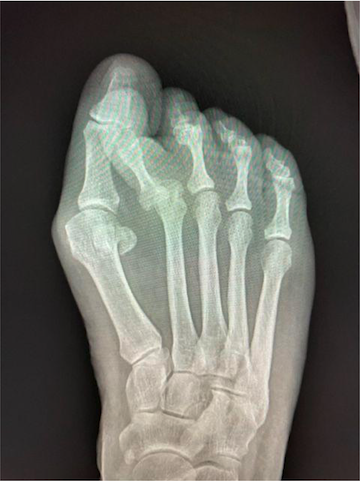

With advancing technology, new emerging bunion techniques have evolved, the newest concept being innovations in minimally invasive surgery (MIS). The question, however, is, “What procedure should surgeons do for a larger bunion deformity?”

Traditionally, surgeons used the Lapidus and proximal osteotomies of the first metatarsal to correct larger bunion deformities. In the last several years, it has become increasingly common to correct larger bunion deformities with distal MIS osteotomies. Here, the authors review the current literature on correcting larger bunion deformities with both Lapidus and MIS techniques.

Severe hallux valgus is categorized as an intermetatarsal (IM) angle of greater than or equal to 20 degrees and a hallux valgus angle (HAV) of greater than 40 degrees.